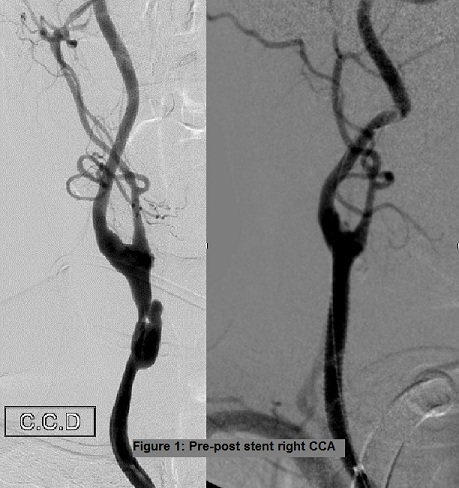

At 2 month we decided to proceed with stenting of the contralateral lesion. A 9F sheath was then positioned within the right common femoral artery. Using a 7F Simmons-3 catheter in combination with a 10F guide catheter, successful catheterization of the left CCA was achieved. We used proximal cerebral protection (Mo.Ma Medtronic™) and distal filter protection. Acculink carotid stent system 5x70mm (Abbot ™) was deployed into the patient’s left CCA. There was immediate improvement of the caliber of the artery (Figure 2).

Figure 2: Pre-post stent left CCA.